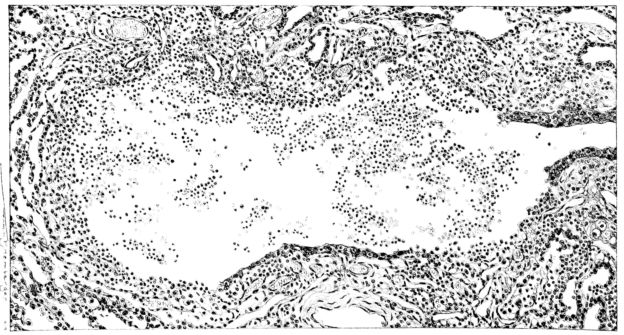

FIG. III. AUTOPSY NO. 90. DRAWING FROM A LESION OF THE TRACHEA (SOMEWHAT OLDER THAN THAT ILLUSTRATED IN FIGURE II). THE MUCOSA IS ENTIRELY LACKING. CONGESTION AND EDEMA ARE THE STRIKING FEATURES IN THE SUBMUCOSA. THE NECROTIZING PROCESS HAS EXTENDED INTO THE MUCUS GLANDS. THIS IS SHOWN IN THE LOWER PICTURE.

The changes are less marked, perhaps, in the trachea than in its finer ramifications. The mucosa is constantly more or less destroyed and large areas, usually focal, are entirely devoid of their epithelial covering. This is replaced by a sparse exudate, composed largely of red blood cells, mucus, a small amount of fibrin, and nuclear fragments (Fig. II). It may dip into the submucosa for a short distance, but usually these indentures are associated with the ducts of the mucous glands into which the inflammatory reaction extends. A more striking feature than the exudate, however, is the edema and the congestion of the submucosa. The loose areolar tissue of the submucosa is spread widely apart, and throughout it distended blood vessels are very conspicuous. Occasionally such a vessel is broken and actual hemorrhage appears in the submucosa. Occasionally, too, the inflammation extends down the duct to the mucous gland itself, and here, also, aplastic inflammatory reaction is evident, inasmuch as the acini now stain intensely red with the cells undifferentiated from each other and specked here and there by broken remains of the dead nuclei (Fig. III). After the disease has continued for a short period, even at the end of five or six days, some regeneration of the epithelial lining may be seen (3) (Fig. IV). But despite this, the acute picture persists, and there goes on, side by side, an attempted repair characterized by epithelial regeneration and the same evidence of acute change. Since the lesion is essentially a superficial one, scars or contractures of any extent are not encountered in the trachea, even in examples of the disease that have ended fatally only after many weeks.[4]